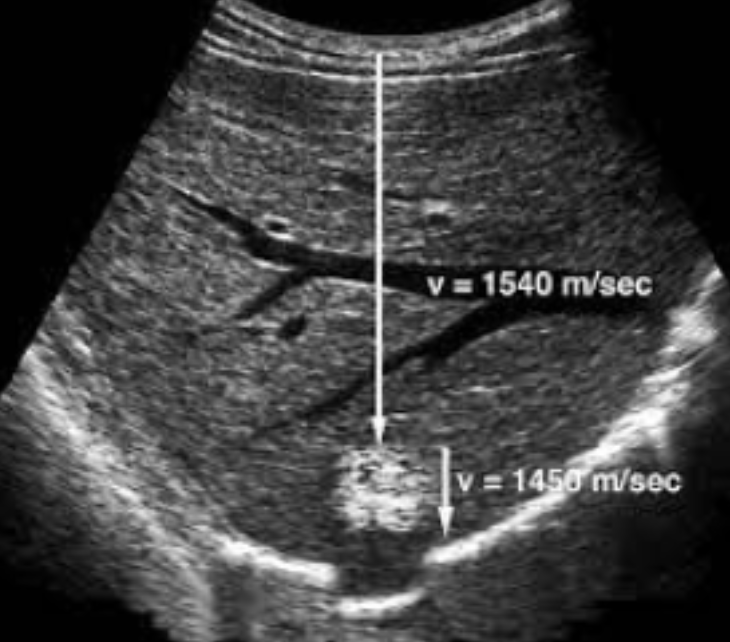

Propagation Speed Error

Caused by a structure of lower or higher velocity than 1540 m/s (what the machine assumes)

Appears as:

Vertical displacement behind area of non-1540 m/s

Faster = shallower

Slower = deeper

Distortion of shape of the object

Cannot be eliminated

The image shows a hemangioma that causes a slower velocity and therefore makes a part of the diaphragm appear deeper than it really is

1540 m/s, Vertical, 1540, shallower, deeper, shape, Cannot